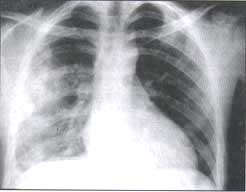

Figura No. 1 Radiografía PA, vertical en un paciente con traumatismos tóraco- abdominal.

Se observa una extensa de opacidad con broncogramas aéreo por ocupación alveolaren el pulmón derecho, por contusión pulmonar. Pequeño neumoperitoneo debajo del hemidiafragma derecho.

Estas contusiones se presentan como lesiones del espacio aéreo, con ocupación alveolar homogénea, periférica y de distribución que no es lobar ni segmentaria (figura No.1). Pueden ser de distribución focal, multifocal, unilateral o bilateral, pero más frecuentemente son unilaterales.